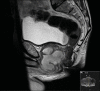

Prostatic abscess (PA) is a rare clinical entity due to a variety of causative organisms including gram-negative bacilli, anaerobic and fungal agents. We report on a 55-year-old, HIV+ patient presenting with a 2-week history of urethral discharge and a large PA. He was successfully treated with a combination of radiological-guided transperineal drainage plus antibiotics. Treatment decisions in patients with PA are multifactorial and should be made with all diagnostic information available from the most current modes of medical imaging. In the case of PA several factors should be assessed, including size of the prostate, size, location and frequency of abscesses, previous pelvic surgery, relevant co-morbidities and risk factors, and patient preference.